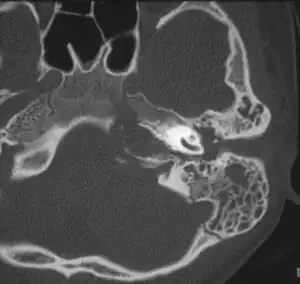

Apicitis petrosa as seen in computed tomography | |

In persons with longstanding ear infection and typical symptoms, medical imaging such as CT or MRI of the head may show changes that confirm disease involvement of the petrous apex of temporal bone.